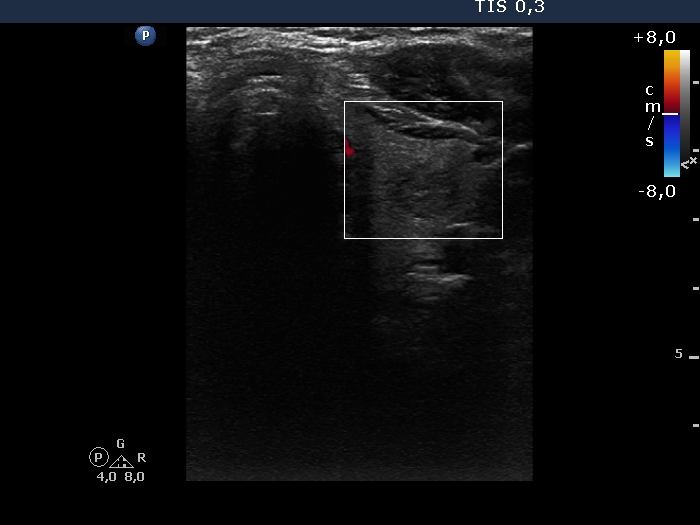

Right lobe, longitudinal scan

Left lobe, transverse scan, color Doppler mode. The lobe and the nodule is avascular.